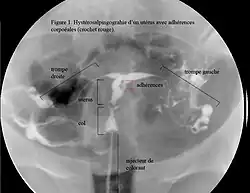

image hystérosalpingographique.

Une aménorrhée avec un historique de curetage pratiqué après une grossesse est typique. L’hystéroscopie est la méthode idéale pour poser un diagnostic[8]. Les images obtenues par hystérosonographies ou par hystérosalpingographie révèlent l’étendue des cicatrices et adhérences (synéchies). L’échographie seule n’est pas une méthode fiable pour le diagnostic du syndrome d’Asherman. Les analyses hormonales montrent souvent des taux normaux compatibles avec les fonctions reproductrices, ce qui élimine la possibilité des troubles menstruels dus aux dérèglements hormonaux.